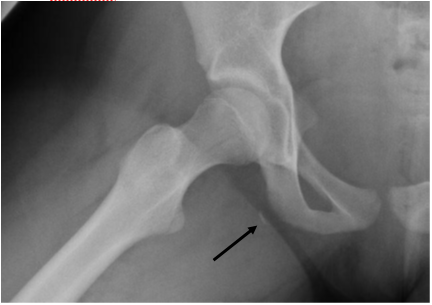

This patient sustained a hamstring avulsion. Diagnosis of such injuries is often missed or delayed, which results in complications such as sciatica, pain, weakness, stiffness, or even deformity.

- Hamstrings are comprised of three muscles: the biceps femoris, the semitendinosis, and the semimembranosis

- Origin of the hamstrings is the ischial tuberosity

- Avulsion injury at the myotendinous junction causes a small sliver of bone to be separated, which visible on the radiograph.